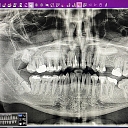

Dentalfix, SIA

Cēsu 19-32, Valmiera, Valmieras nov., LV-4201

Zobārsts Valmierā